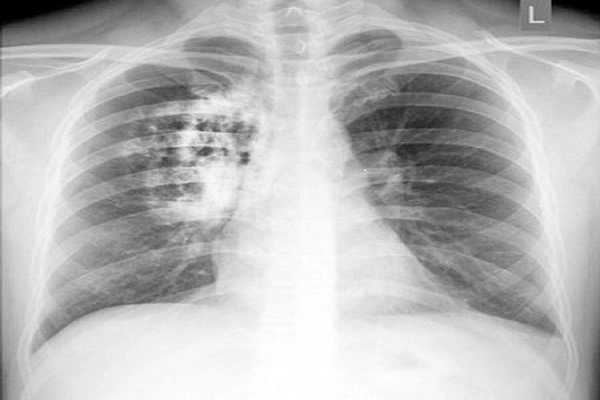

Bạn sẽ phải rùng mình khi chiêm ngưỡng hình ảnh bệnh lao phổi là như thế nào dưới ống kính y học thực tế. Những bức ảnh chụp X-quang cho thấy phổi bị tổn thương nặng, xuất hiện những đốm trắng mờ như bóng ma ám ảnh. Không chỉ là các tổn thương vật lý, đây còn là những “chứng tích sống” của căn bệnh âm thầm hủy hoại cơ thể qua từng hơi thở. Từ viêm nhẹ đến tổn thương lan rộng, hình ảnh bệnh lao phổi khiến người xem không thể rời mắt vì mức độ nghiêm trọng mà nó thể hiện rõ ràng qua từng chi tiết.

Cảnh báo: tổng hợp ảnh bệnh lao phổi chân thực này không dành cho người yếu tim. Đây là loạt hình ảnh y khoa được các chuyên gia sưu tầm và xác thực, ghi lại quá trình tiến triển của bệnh từ giai đoạn đầu đến giai đoạn nguy kịch. Từng mảng mô phổi bị ăn mòn, xơ hóa, hoại tử được phơi bày rõ nét dưới ánh sáng X-quang lạnh lùng. Những hình ảnh này không chỉ mang tính chất minh họa y học, mà còn là hồi chuông cảnh tỉnh cho bất kỳ ai còn lơ là với căn bệnh nguy hiểm này.